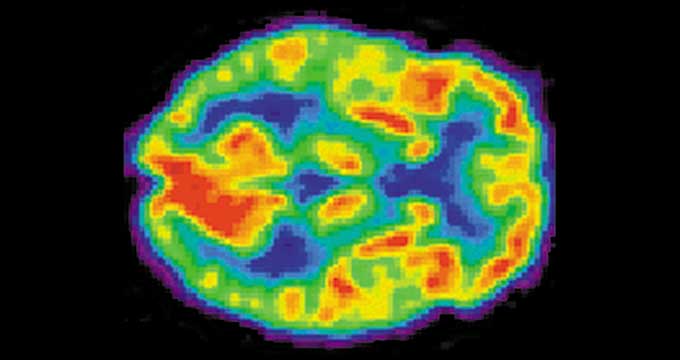

The article in New Scientist, which I have linked to below, as well as the scientific journal it cites, which I have also linked to below, make a very bold claim. Before going into the claims, however, we need to explain how the study was performed. In two separate studies, researchers brought in around thirty early twenties adults of roughly equal gender disparity. These test subjects were each presented, in a random order, with thirty-six different projects from the online fundraising platform, kickstarter. Each subject was shown the same thirty-six projects. They were asked to select either a yes or no to the question of whether they would fund each project. The test subjects were given seconds to make this determination. While viewing each project, the subjects underwent an MRI brain scan, to determine brain activity. After viewing each project, the subjects rated their response to that project. The results were somewhat expected. Test subjects chose to fund projects they either liked or thought would be successful. However, the tests subjects ability to guess which projects would succeed was only about 52.9 percent. If the experiment were conducted across the whole population, this is close enough to the average that it would likely regress to 50 percent. However, during the brain scan, a region of the brain, called the nucleus accumbens, was active. The activity in this region was predictive of kickstarter project success 59.1 percent of the time. This is well outside the potential regression to pure guesswork. The researchers repeated the study with different test subjects and got similar results. This led them to believe that the nucleus accumbens can be used to predict how the market will react to a given product.

If the researchers are correct, then the brain is smarter than our decision-making process. However, the research for what is called “neural forecasting” is still in its infancy so it is too early to make any assumptions. Further, the term “predict the future” is plastered in the title of the New Scientist article. 59.1 percent accuracy is better than pure random luck, but it is far from the standard of predictive. This near 60 percent accuracy still means that the nucleus accumbens is wrong 40 percent of the time. While the brain may be a bit better than its owner at making choices, it is not remotely close to predictive. Neural forecasting can certainly be an aid to decision making and perhaps further experiments will demonstrate results much higher than the near 60 percent demonstrated in this study. However, until such time as neural forecasting can predict with above 85 percent certainty that something will be successful, it will remain a mere aid, and expensive one at that, to the human cognitive process.